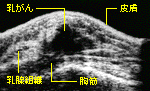

乳がん初期に威力を発揮するマンモグラフィーによる診断

ふつうよりも波長の長いX線を使用したX線の乳房の撮影を、マンモグラフィーという。乳がんの初期など、従来のX線には写らない小さながん組織の影も、小さい石灰化の像の存在で発見できる。左上は、乳がんの超音波画像。